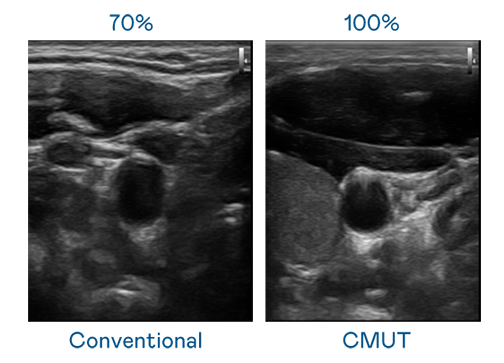

CMUT 技术是一种用电容式微机电元件来产生超音波讯号的技术。与传统 PZT 压电式技术相比,CMUT 频宽增加 30%,更宽频的超音波讯号让影像解析度大幅提升,是实现高影像品质医疗超音波扫描、促进精准医疗发展的关键技术。

超音波影像的解析度高低,首先取决于探头能发出的讯号频宽。J9国际站 CMUT 可提供高清晰的超音波讯号,提供高频宽、高灵敏度、影像纹理细节更高的超音波影像,协助医护人员缩短影像判读时间及利用精准的医疗影像进行诊断。